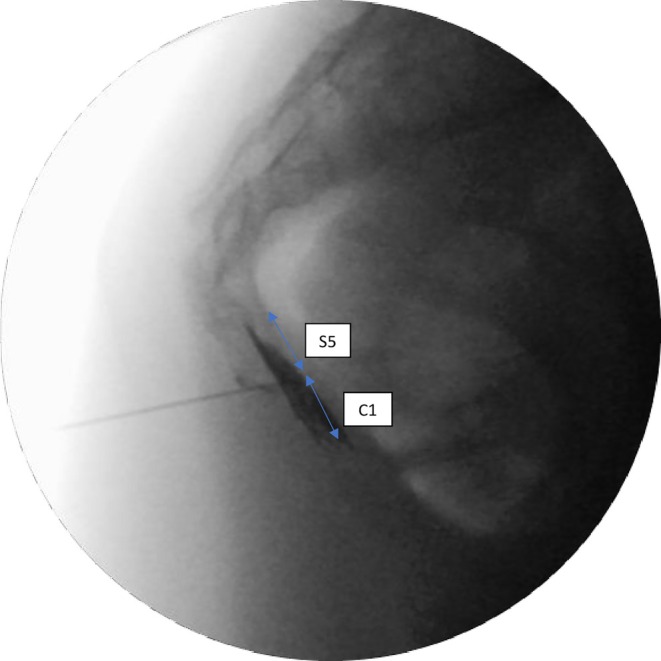

Abstract Image